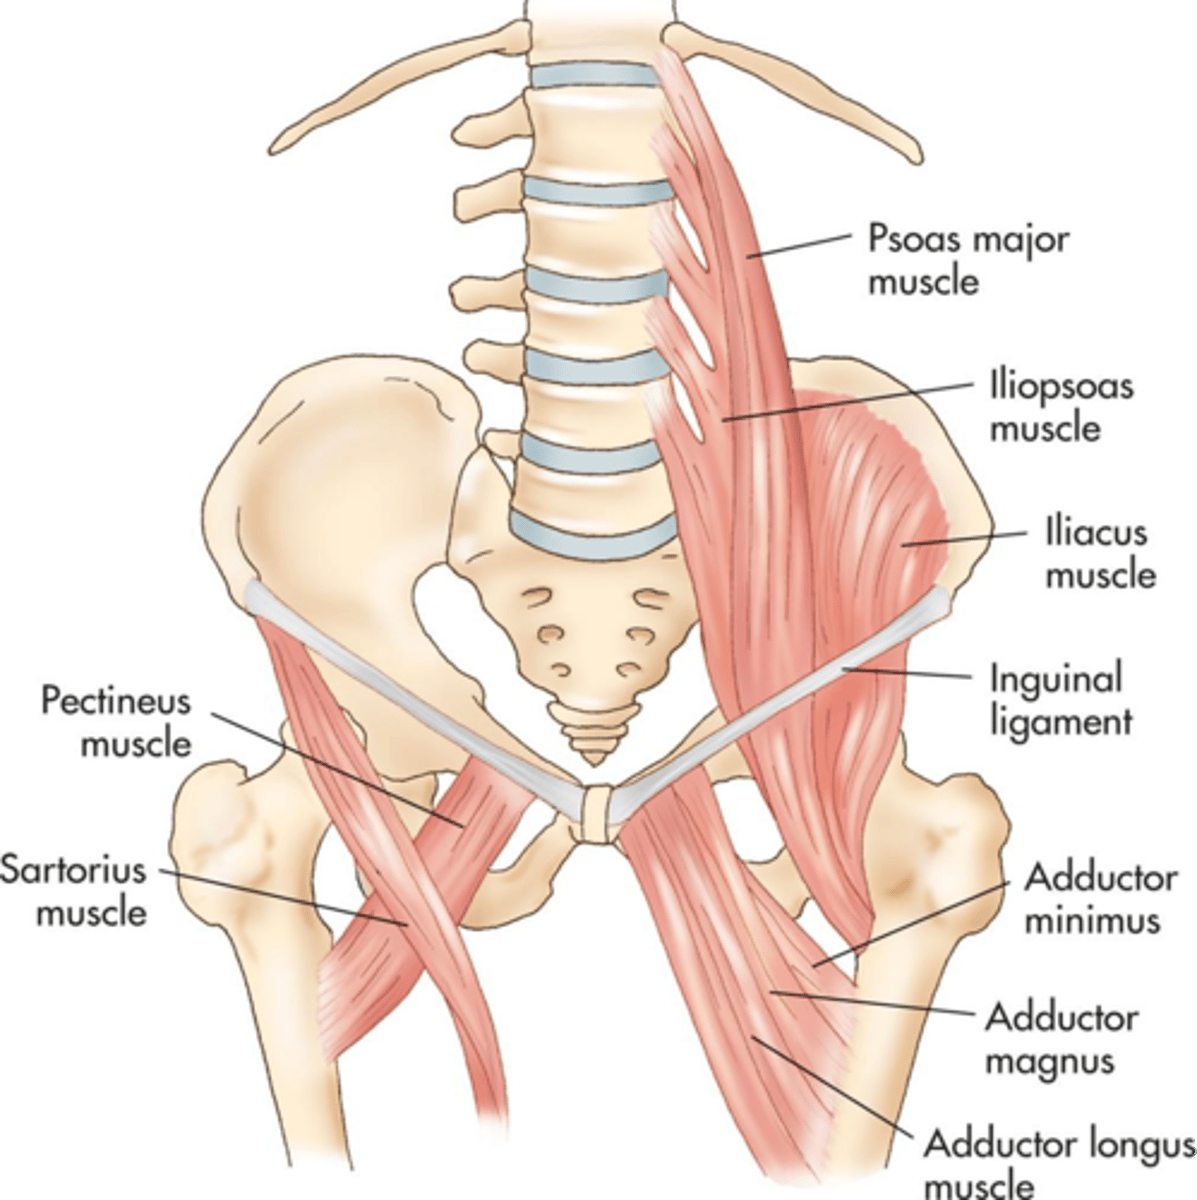

Psoas muscles extend from the ___ aspects of the lumbar vertebrae across the ___ abdominal wall to the ___

lateral; posterior; iliac crest

Illiopsoas muscles travel ___ from the psoas to insert into the ___ of the femur

anteroinferior; lesser trochanter

Obturator internus muscles line the ___ walls of the true pelvis

lateral

Piriformis muscles are in the ___ region of the true pelvis behind the ___

posterior; uterus

What muscle is often mistaken for ovaries?

piriformis